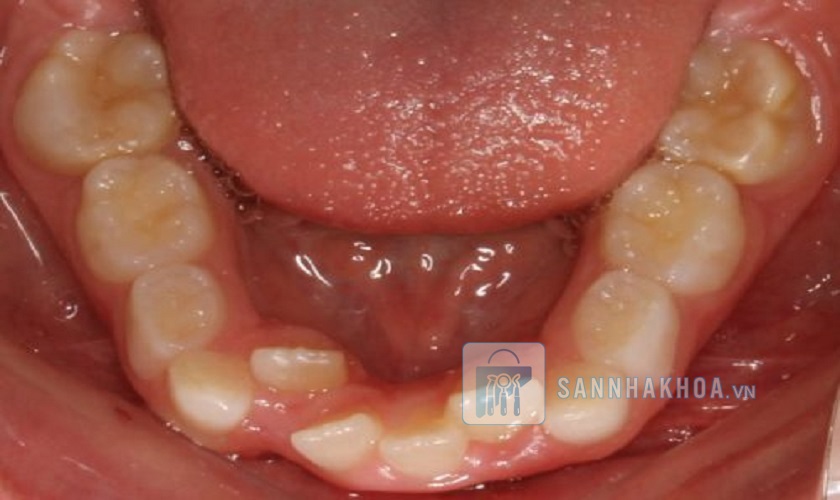

Răng vĩnh viễn mọc vào lúc mấy tuổi?

Răng vĩnh viễn mọc dần từ 6 tuổi và hoàn thiện khi người trưởng thành, trong đó răng khôn là chiếc răng mọc cuối cùng. Quá trình phát triển này cho phép xương hàm mở rộng, tạo đủ không gian cho răng mọc đúng vị trí. Tuy nhiên, nếu răng vĩnh viễn mọc lệch hoặc không đủ không gian, có thể gây sai khớp cắn, chen chúc răng hoặc các vấn đề về thẩm mỹ và chức năng.

Mối liên quan này được thể hiện rõ qua sự kết nối giữa mầm răng vĩnh viễn và răng sữa. Trong giai đoạn phát triển của trẻ, mầm răng vĩnh viễn nằm ẩn bên dưới răng sữa. Khi đến thời điểm thay răng, chân răng sữa bị tiêu biến, tạo điều kiện cho răng vĩnh viễn trồi lên. Nếu răng sữa bị mất quá sớm do chấn thương hoặc sâu răng, răng vĩnh viễn có thể mọc lệch lạc, gây sai khớp cắn và ảnh hưởng đến cấu trúc hàm mặt.